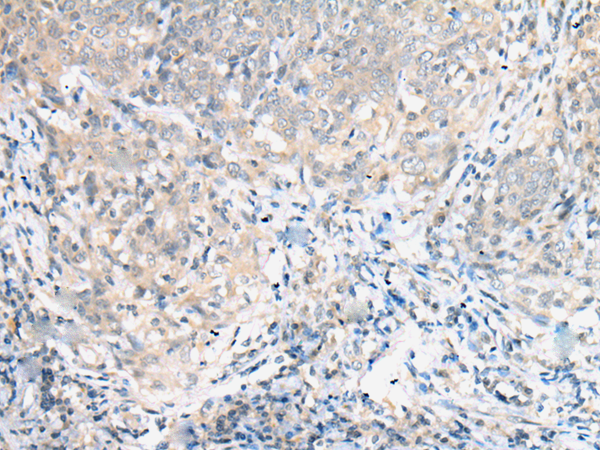

分类: 科研抗体货号: P09096别名:应用: IHC反应种属: Human